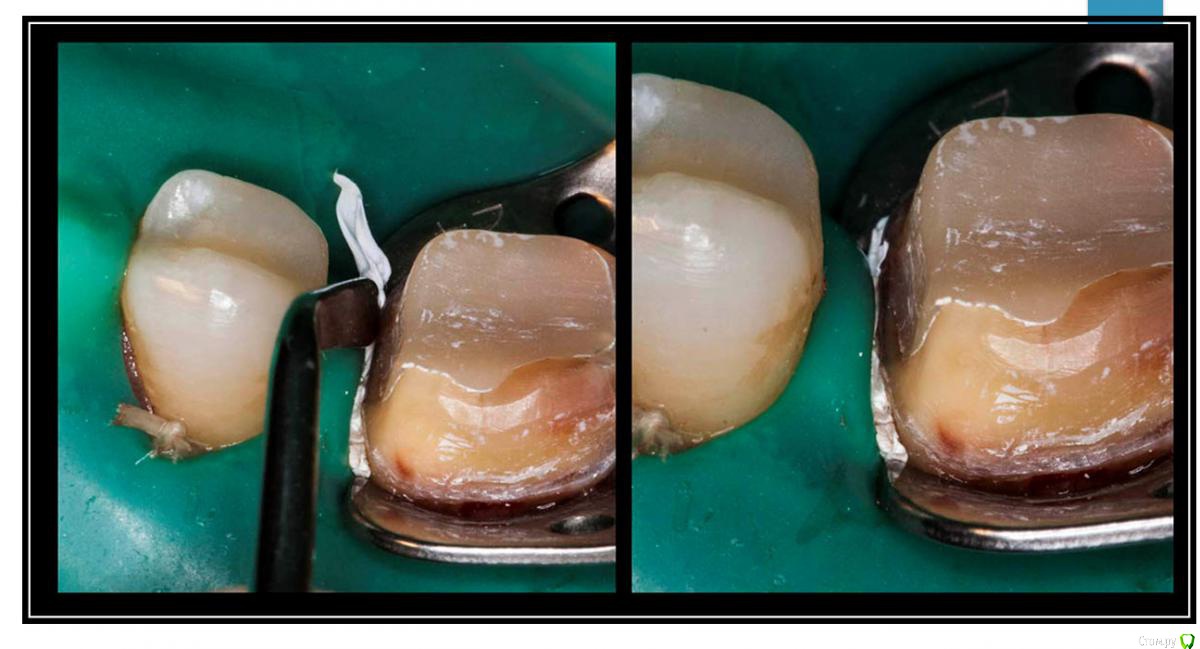

Гарриевич Опубликовано 12 апреля, 2016 Поделиться Опубликовано 12 апреля, 2016 (изменено) посмотрел фотки, оказывается я вот так делаю почти всегда получается так, но это для эндоно при реставрациях так можно Изменено 12 апреля, 2016 пользователем Гарриевич 5 Ссылка на комментарий

ger_berra Опубликовано 12 апреля, 2016 Поделиться Опубликовано 12 апреля, 2016 посмотрел фотки, оказывается я вот так делаю почти всегда IMG_6535.jpgполучается так, но это для эндоIMG_6668.jpgно при реставрациях так можноIMG_6605.jpgIMG_6612.jpgтефлон-наше фсё!!! Ссылка на комментарий